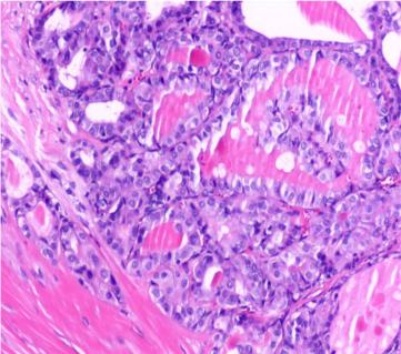

(a) (b) (c) (d)

(i) (j) (k) (l)

(i)~(l)甲状腺乳头状癌患者双能量CT增强扫描动脉期原始图像、碘图、Rho/Z图及病理图

Figure 1. Examples of dual-energy CT arterial phase images, iodine uptake images, Rho/Z images, and pathological findings in three groups of patients with thyroid nodules (HE, ×100, H) (Rho/Z, Electron Density/Effective Atomic Number)

1. 三组甲状腺结节患者双能量CT动脉期图、碘图、Rho/Z图及病理图示例(HE, ×100, H) (Rho/Z,电子密度云/有效原子序数)